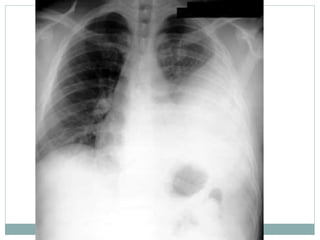

Avalie o raio x , descreve bem a

patologia cardiaca,

Conclusão?

Tecnica:

rotada, pouco penetrado,

revelação boa, tirado deitado e inclinado

Patologia:

• Cardiomegalia grave,

• com atrio esquerdo muito prominente

• Ventriculo esquerdo e atrio direito também

dilatados

• Trama vascular aumentada

Conclusão:

(11 anos, clinicamente IC que agravou ha uma semana)

Raio X tipico de insuficiencia mitral (provavelmente devido FR) com IC

descompensada

• NB como a penetracao é muito diminuida corremos risco de “ ver” lesões

pulmonares amais, neste caso não ha infiltrado pulmonar, apenas congestão

pulmonar!